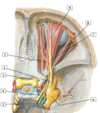

1 - stylohyoid muscle

1 - Digastric muscle

1 - trochlear nerve (IV)

2 - ophthalmic nerve (V1)

3 - optic nerve (ii)

4 - oculomotor nerve (iii)

5 - abducent nerve (VI)

6 - trigeminal (semilunar) ganglion

7 - frontal nerve

8 - lacrimal nerve

9 - supra-orbital nerve